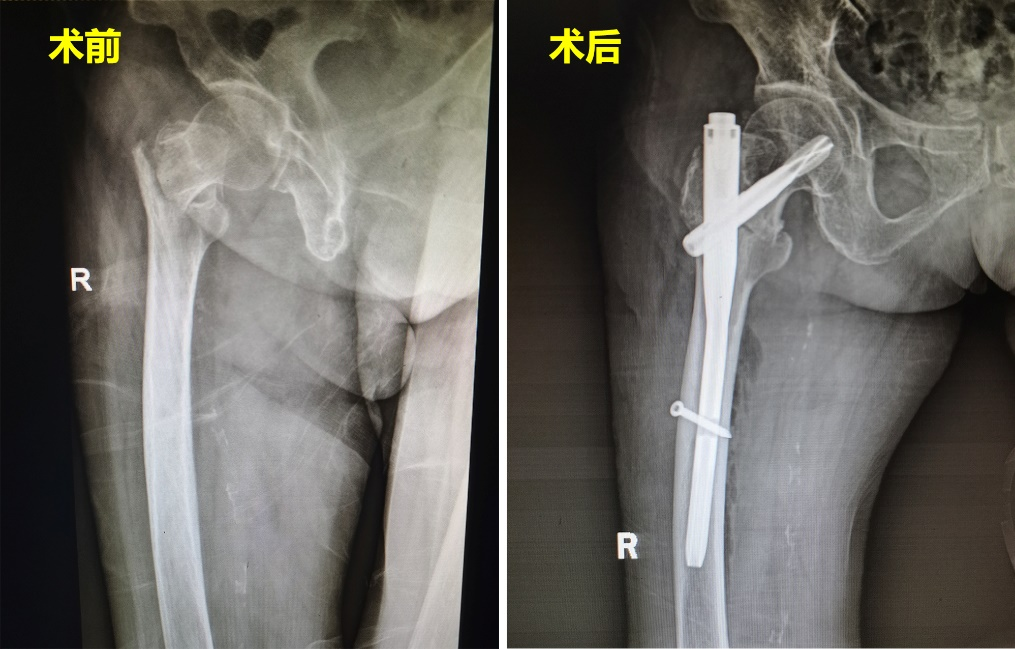

7月3日,怀揣着希望,杨奶奶一家人慕名来到了中南大学湘雅三医院创伤骨科就诊。罗令教授了解情况后,紧急启动了老年髋部骨折多学科合作(Multiple Disciplinary Team,MDT)团队,为杨奶奶开通绿色通道,当日即行全院大会诊。在经过医院骨科、麻醉科、消化内科、心血管内科、手术室及护理团队充分、完善的术前准备后,罗令教授全程穿戴30余斤重的铅衣,利用独创的转子间骨折治疗的经验,全程在G臂透视下进行定位,大大缩短手术时间,手术用时仅21分钟,手术总切口长度不足5公分,出血量不足30ml,高质量完成了骨折内固定手术。患者术后恢复情况良好,第二天即下地行走,患者本人及家属对手术效果非常满意。术后,杨奶奶紧紧抓着罗令教授的手,反复念叨着说没有走错地方,感谢罗令教授团队的及时救治。

我国是世界上老年人口规模最大的国家,老年髋部骨折发生后一年,存活率仅有30%,因此,以股骨转子间骨折为代表的老年髋部骨折也被称为“人生中最后一次骨折”。基于此,国际指南要求老年髋部骨折在伤后48小时内应尽快完成手术,并尽早进行康复锻炼。中南大学湘雅三医院的老年髋部骨折MDT团队在处理此类难题时具有丰富的“新湘雅”经验。医院骨科主任吴松、副主任罗令与麻醉科等各科室协同合作下制定出合理周密的手术方案,同时,骨科护士长杨驰带领护理团队为患者制定出个性化的护理计划,实施ERAS快速康复护理模式,并根据患者的具体情况落实有效的康复训练。最终,罗令教授团队不负众望,杨奶奶获得了及时并有效的治疗。